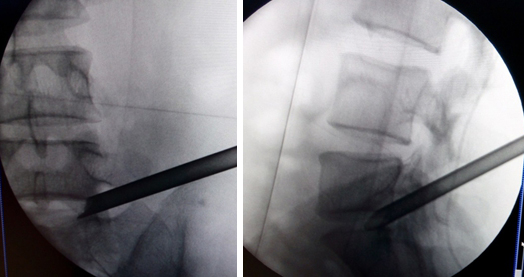

(图)体表定位

(图)穿刺针定位

(图)置入扩张管

(图)术中